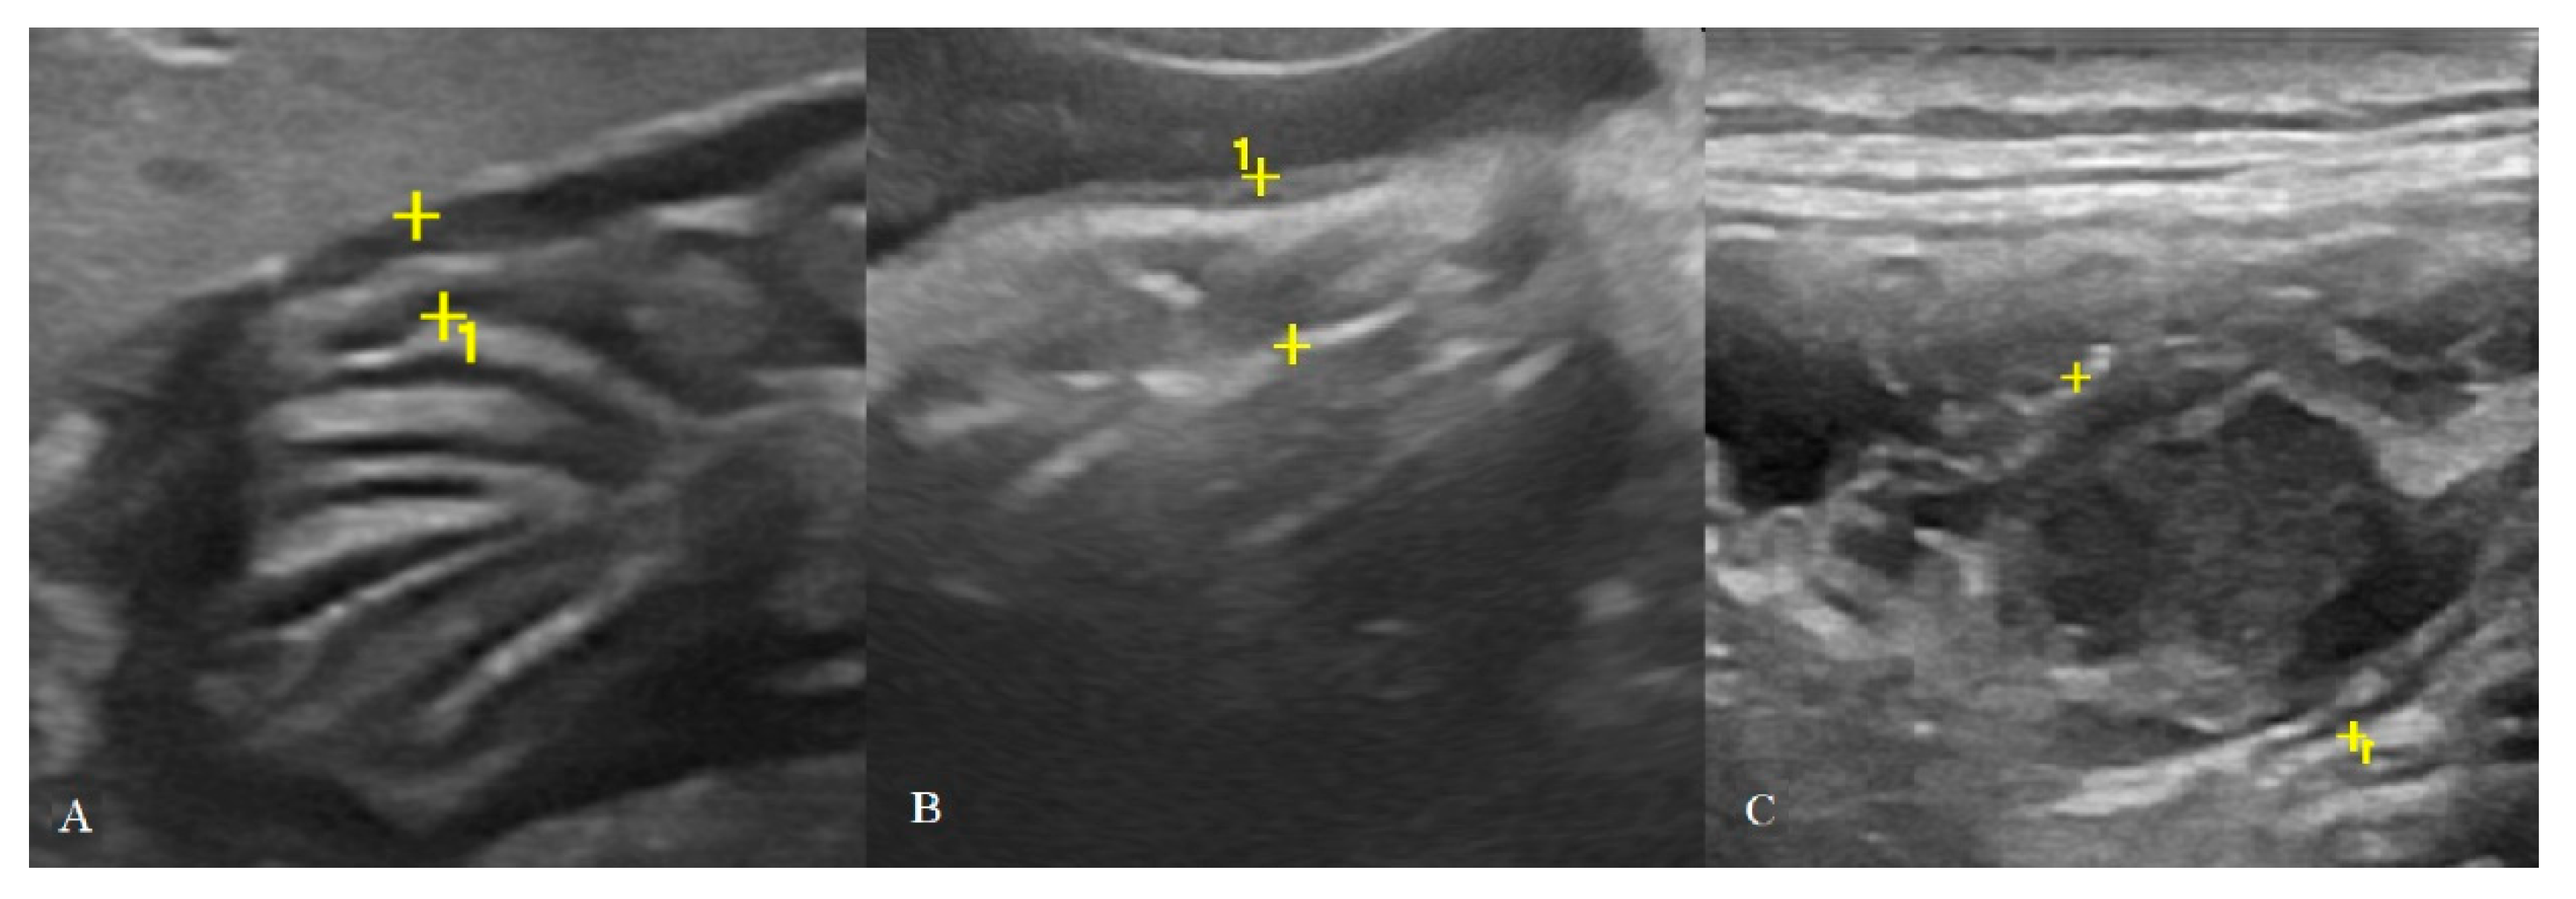

Figure 2. Cat affected by gastric low-grade lymphoma (LGAL) showing: (A) diffuse reduced layer definition associated with mild increases in wall thickness (3.8 mm between the asterisks) on B-mode examination; (B,C) B-mode (B) and contrast-enhanced ultrasonography (CEUS) (C) clip acquired using dual-mode visualization in order to better identify the gastric wall during CEUS examination.

Figure 5. Classification of gastric wall layer definition on B-mode US: (A) normal: all the five layers are easily identified and thickness is normal (2.4 mm between the cursors in a HEA cat); (B) reduced: the identification of the layers is more difficult and, in some portions, it may not be evident, in addition to a mild diffuse wall thickening (3.6 mm between the cursors in a INF cat); (C) absent: it is not possible to recognize the normal wall stratification and layer definition is lost. Here, a focal transmural mass (16.5 mm between the cursors in a HGAL cat) with mixed echogenicity is also present.